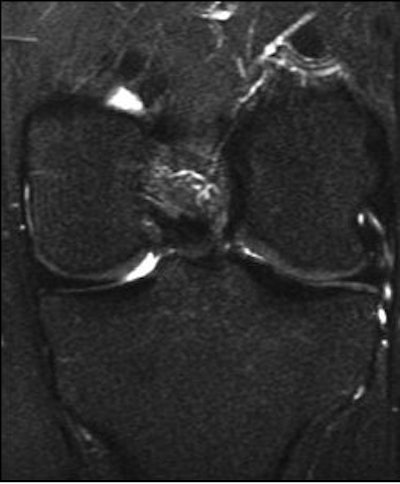

| A 31-year-old man with fast resolution of bone bruise, reticular lesion type. Coronal T2-weighted fast-suppressed images (TR/TE, 12/3,700; fat saturation; section thickness, 3 mm; field-of-view, 180 x 135 mm; matrix, 385 x 224) show fast resolution of bone bruise from baseline (above), to three-week follow-up (middle), and at nine-week follow-up (below). |

![]() |